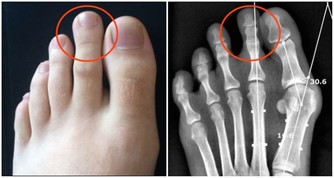

8、膝蓋左右腳的腳後跟外側部分和膝蓋是有直接關連的,

如果你是

膝蓋酸痛或慢性膝關節疼痛的患者,可以試著按摩這個區域來減緩疼痛。